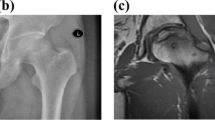

The results of X-ray, CT and MRI images were typically matched with the ONFH histopathological reviews. The X-ray, CT, and MRI images of hip joint were used for clinical diagnosis. And the microscopic images (4×) of eosin-stained and hematoxylin sections of ONFH bone specimen were used for histopathological diagnosis. All the images were presented in Fig. 1. In Fig. 1a, collapse of the femur head was showed in the plain radiograph obtained from the ONFH patients. In Fig. 1b, the trabecula fracture of ONFH femoral head was presented in CT. In Fig. 1c, the typically subchondral fracture as a band of low signal intensity was displayed in T1-weighted MRI image. In Fig. 1d, pathological section showed the lesion region of ONFH femoral head.